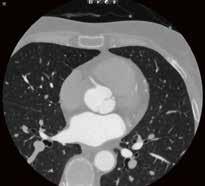

Low-Dose-Thorax-CT als Verlaufskontrolle bei Lungenkarzinom unter Immuntherapie. Aus der Anfangsphase der Implementierung von AiCE im klinischen Alltag zeigt sich bei vergleichbarer Dosis eine bessere Bildqualität mit besserer Detailauflösung im Bereich des Lungenparenchyms, hier im Bereich der strahligen Ausläufer des Tumors und an den direkt angrenzenden Bronchialstrukturen gut zu erkennen.

Fall 4: Fall 5:

Einer der ersten Patienten, die nach der Installation der AiCE-Algorithmen untersucht wurden. Hier wurde zum Vergleich aus derselben Untersuchung jeweils eine Rekonstruktion mittels AIDR 3D und eine Rekonstruktion mit AiCE angefertigt. Auch hier fällt die bessere Detailauflösung, beispielsweise im Bereich der Interlobulärsepten oder der Emphysembullae, auf. //

Abb. 5 a: Low-Dose-Thorax-CT, Canon Aquilion Prime SP, Rekonstruktion: AIDR 3D; DLP 115,8 mGy × cm / 2,1 mSv Abb. 4 a: Low-Dose-Thorax-CT, Canon Aquilion ONE, Rekonstruktion: AIDR 3D; DLP 55,1 mGy × cm / 1,0 mSv Abb. 5 b: dieselbe Untersuchung, Rekonstruktion: AiCE Abb. 4 b: Low-Dose-Thorax-CT, Canon Aquilion Prime SP, Rekonstruktion: AiCE; DLP 65,7 mGy × cm / 1,2 mSv